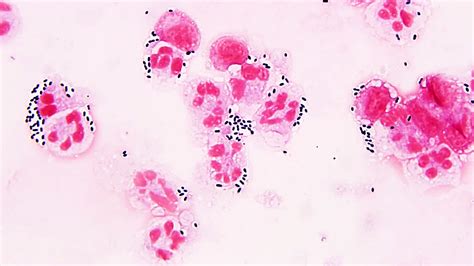

Alright, let’s start with the basics. Streptococcus pseudoporcinus is a type of bacteria that, while not super common, can cause infections in humans. Think of it like a less-famous cousin of other, more well-known Streptococcus bacteria. It’s often found in places like the skin and mucous membranes. The key thing to remember is that it’s an opportunistic pathogen, meaning it tends to cause problems when your body’s defenses are down, like if you’re already sick or have a weakened immune system. It can cause various infections, and it’s essential to understand the specific symptoms and how to get the right diagnosis and treatment. The most common infections are related to endocarditis, though it could impact other areas of the body.

So, where does it like to hang out? Well, this bacteria can be found in various environments, sometimes even in healthy individuals. However, it’s when it finds an opportunity, like an open wound or a weakened immune system, that it can cause an infection. The infections can range from mild to severe, depending on various factors, including the infection site and the overall health of the person affected. It can potentially lead to more severe conditions, like endocarditis, an infection of the heart valves.

Knowing the signs and getting a proper diagnosis are super important. The symptoms of a Streptococcus pseudoporcinus infection can vary depending on where the infection is located. Common symptoms include fever, chills, and fatigue. If the infection involves the heart (endocarditis), symptoms might include heart murmurs, shortness of breath, and chest pain. If you suspect you might have an infection, it’s essential to see a doctor right away. They’ll likely take a blood sample or a sample from the infected area to run some tests. To diagnose a Streptococcus pseudoporcinus infection, the doctor will often use a blood culture. This involves taking a blood sample and growing any bacteria present in a lab. The lab can then identify the specific type of bacteria causing the infection. Other tests, like an echocardiogram (an ultrasound of the heart), might be used to check for heart damage.